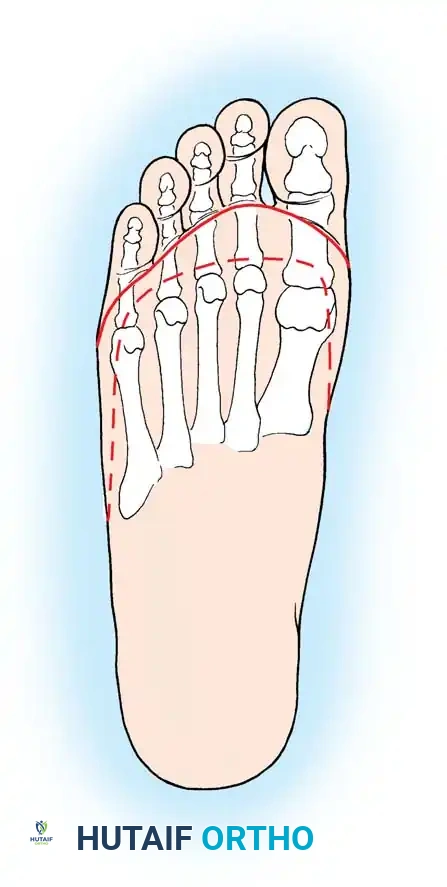

ALTERNATIVE HINDFOOT AMPUTATIONS: BOYD AND PIROGOFF

While the Syme amputation is the gold standard, the Boyd and Pirogoff amputations offer alternative methods of achieving an end-bearing stump, primarily by retaining a portion of the calcaneus to prevent heel pad migration.

The Boyd Amputation

The Boyd amputation produces an excellent end-bearing stump and completely eliminates the risk of posterior heel pad migration because the heel pad remains naturally attached to the retained calcaneus.

- Technique: The procedure involves a complete talectomy. The calcaneus is then shifted forward into the mortise, and a formal calcaneotibial arthrodesis is performed.

- Disadvantages: The required arthrodesis makes this procedure technically much more demanding than a Syme amputation. Nonunion of the calcaneotibial fusion is a significant risk. Furthermore, it produces an even more bulbous stump than the Syme, though modern prosthetists have designed cosmetically acceptable, specialized prostheses to accommodate it.